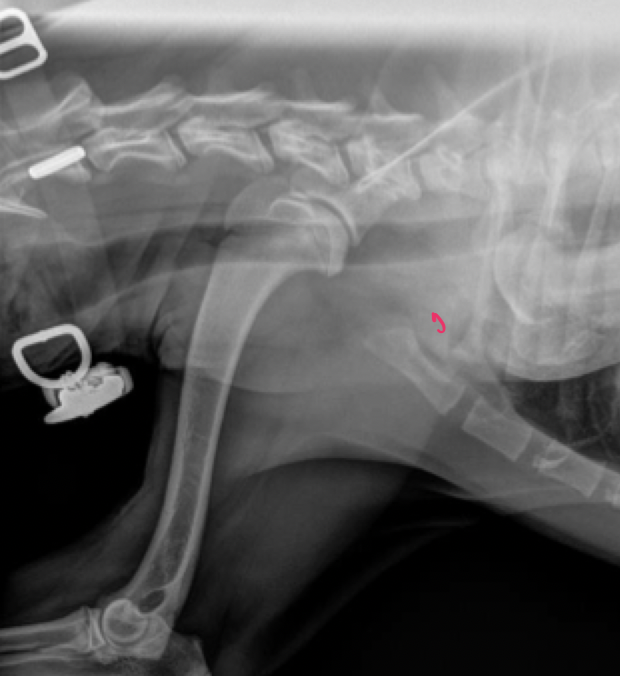

Rt. Femoral Capital Physeal Fracture

muscle atrophy evident on the Rt. leg

Salter harris type 1

delayed physeal closure in early neutered male